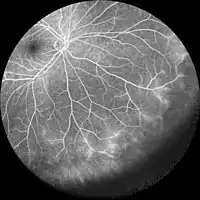

Fluorescein angiography

Optical coherence tomography angiography (OCTA) and Fluorescein angiography to visualize the vascular networks of the retina and choroid.